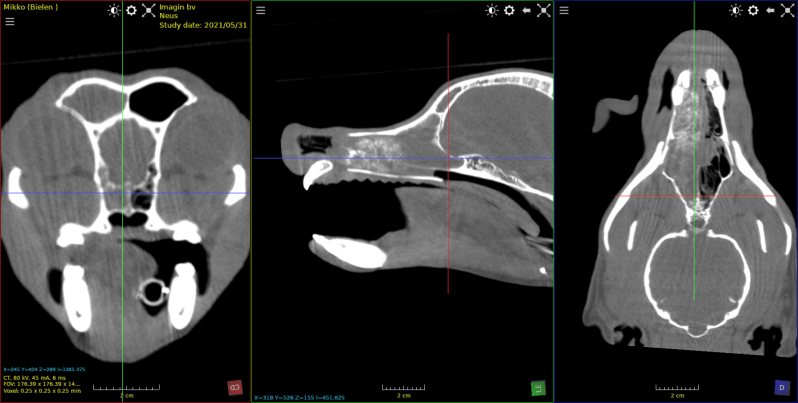

Keeshond van 5 jaar met een adenocarcinoom in de neus

beeld na toediening van contrast . Captatie van contrast in tumor

Aspergilose neus : vernietiging van de conchae rechter neusgat en aantasting botstructuur

Hond met neus tumor , Eenzijdige volledige vernietiging van de conchae; doorbreken tot in sinussen . Boorbraak beelderige structuren neus .